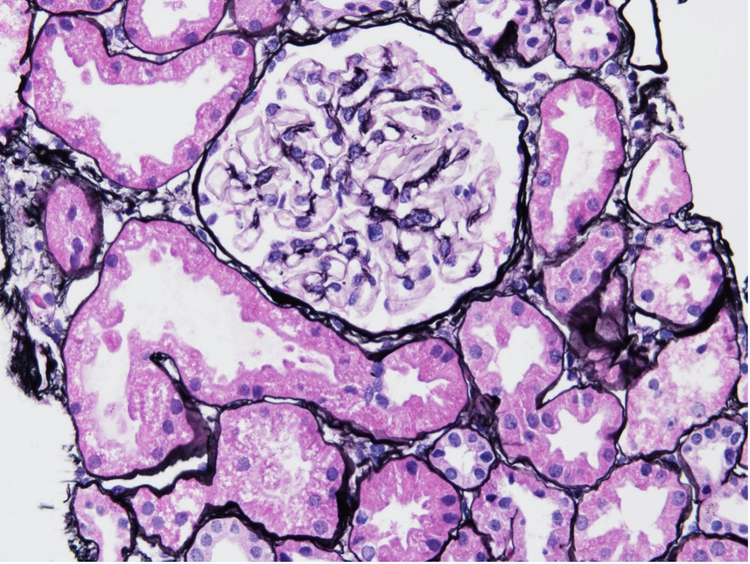

例えば、図1はLNクラス1の初期段階の患者の腎臓サンプルを示していて、健常者と比べて糸球体の目立った変化は見られません。2

図1:Jonasシルバー染色剤で染色されたLNクラス1腎生検サンプル